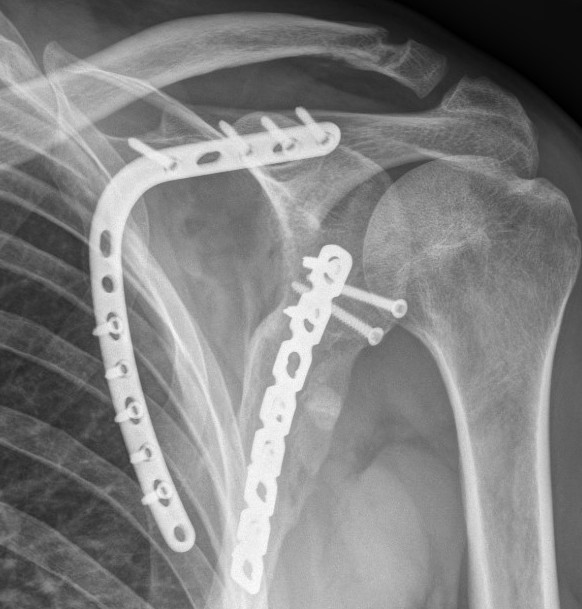

![]() |

Technique

Plates

- lateral border scapula

- scapula spine

- medial border scapula